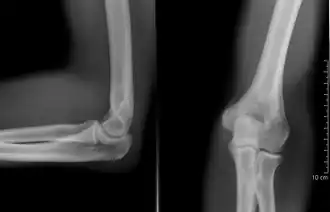

Ellbogengelenk

Das Ellbogengelenk, auch Ellenbogengelenk, (lateinisch Articulatio cubiti („Gelenk des Ellbogens“), von altgriechisch κύβιτον kýbiton, deutsch ‚Ellenbogen oder Ellbogen‘) ist ein zusammengesetztes Gelenk (Articulatio composita) im Arm. Es besteht funktionell aus drei Teilgelenken mit einer gemeinsamen Gelenkkapsel, bei denen der Oberarmknochen (Humerus) und die beiden Unterarmknochen Speiche (Radius) und Elle (Ulna) jeweils mit je einem der beiden anderen Knochen in Verbindung tritt. Der Unterarm kann im Ellbogengelenk gegenüber dem Oberarm gebeugt und gestreckt werden. Darüber hinaus ist das Gelenk funktionell an den Umwendebewegungen der Hand, der Pronation und Supination, beteiligt. Diese werden unter anderem durch eine komplexe Drehbewegung der Speiche ermöglicht. Die Region auf der Beugeseite des Ellbogens heißt Ellenbeuge.